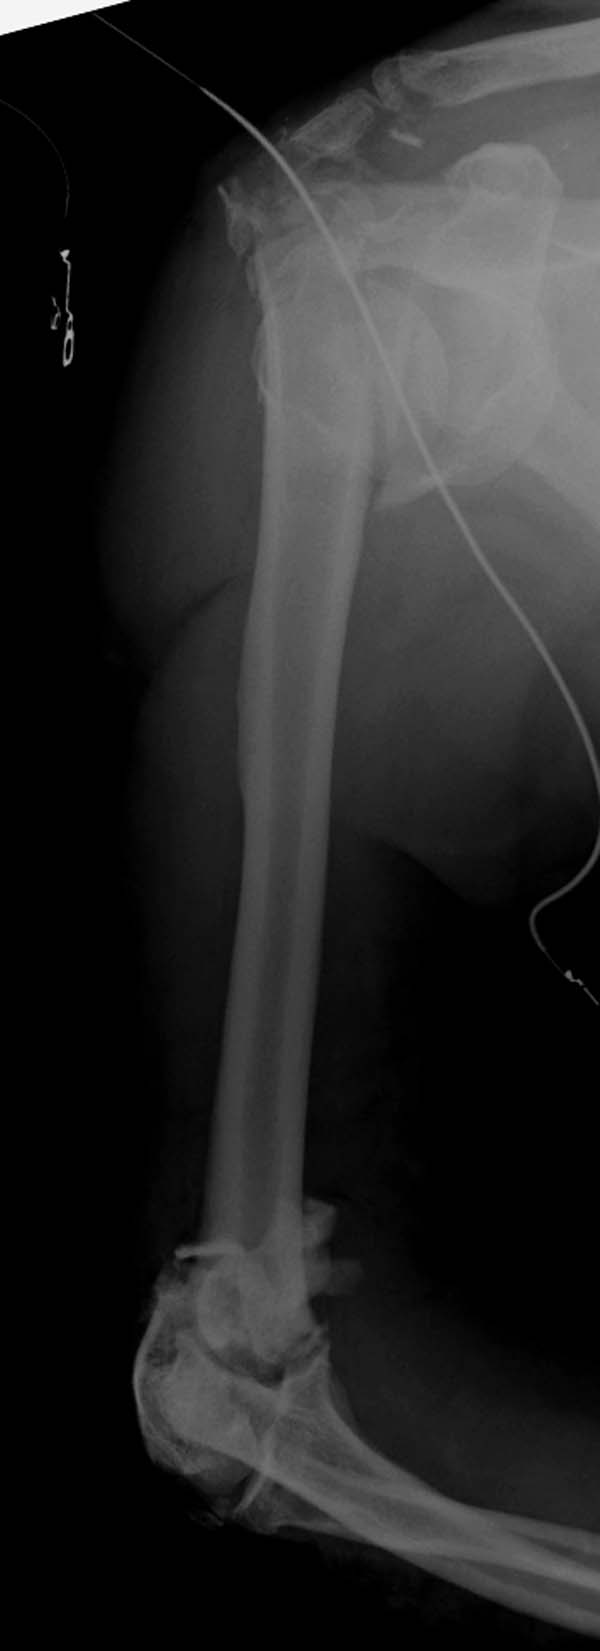

Примеры: первому более 15 лет фиксирован шурупом и tension band

technique, а второй перелом открытый больной 80 лет, после наружного

фиксатора в первом этапе и окончательная фиксация вторично. Третьий раз

внесуставная остеотомия...

Вложение не в текстовом формате было извлечено&hellip;

Имя     : 3-2 Humerus prox distal exfix.jpg

Тип     : image/jpeg

Размер  : 43483 байтов

Описание: отсутствует

Url     : http://weborto.net:8080/pipermail/ortho/attachments/20130604/c45a379f/attachment-0028.jpg